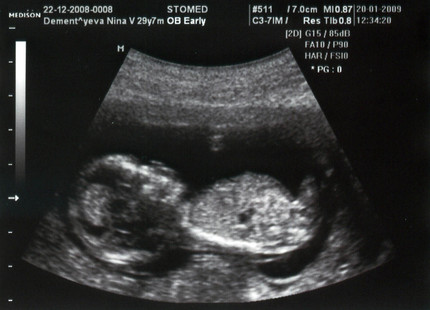

תצפיות דוקטור

בהרשמה במועד, אין צורך בבחינות מתוזמנות בשבוע הארבעה עשר. הרופא ייתן הוראות לבדיקות או ירשום אולטרסאונד רק במידת הצורך. כאשר בדיקת אולטרה-סאונד של נשים בהריון מתעניינת לעתים קרובות בשאלה - ילד או ילדה? בתקופה של 14 שבועות להריון, עדיין קשה מאוד לקבוע את מין התינוק.

צילום אולטרסאונד:

אולטרסאונד -14 שבוע